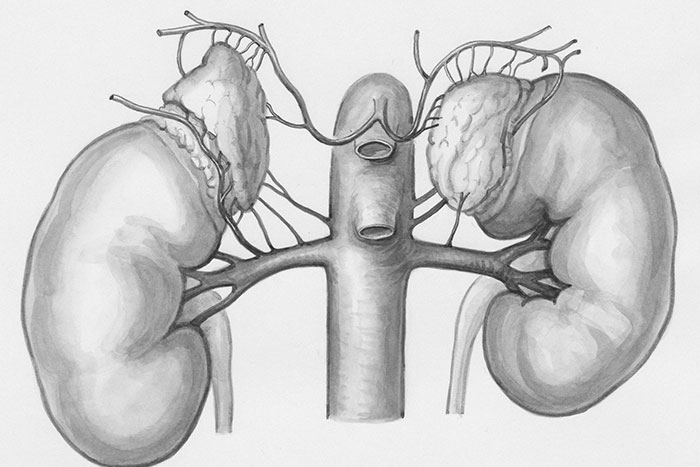

When you get a kidney transplant, unless your original kidneys are diseased, they just lEAVE THE OLD ONES IN THERE. OLD DEAD KIDNEYS JUST CHILLING

also- fallopian tubes are not connected to ovaries. they just float in the general direction of the ovaries and do their best to vacuum up eggs as they get popped out (kind of like a pimple bursting) out of ovary pores? so the eggs just get popped wherever and you gotta cross your toes and hope your weird little vacuum tubes are aiming right that day???

Image credits: fleatsd